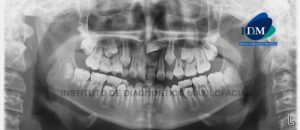

Paciente femenino de 11 años de edad, es referido al Instituto de Diagnóstico Maxilofacial – IDM (Sede Surco) para evaluación tomográfica de pieza supernumeraria. En

Paciente femenino de 9 años de edad, es referido al Instituto de Diagnóstico Maxilofacial – IDM (Sede Surco) para evaluación tomográfica por presentar retraso de